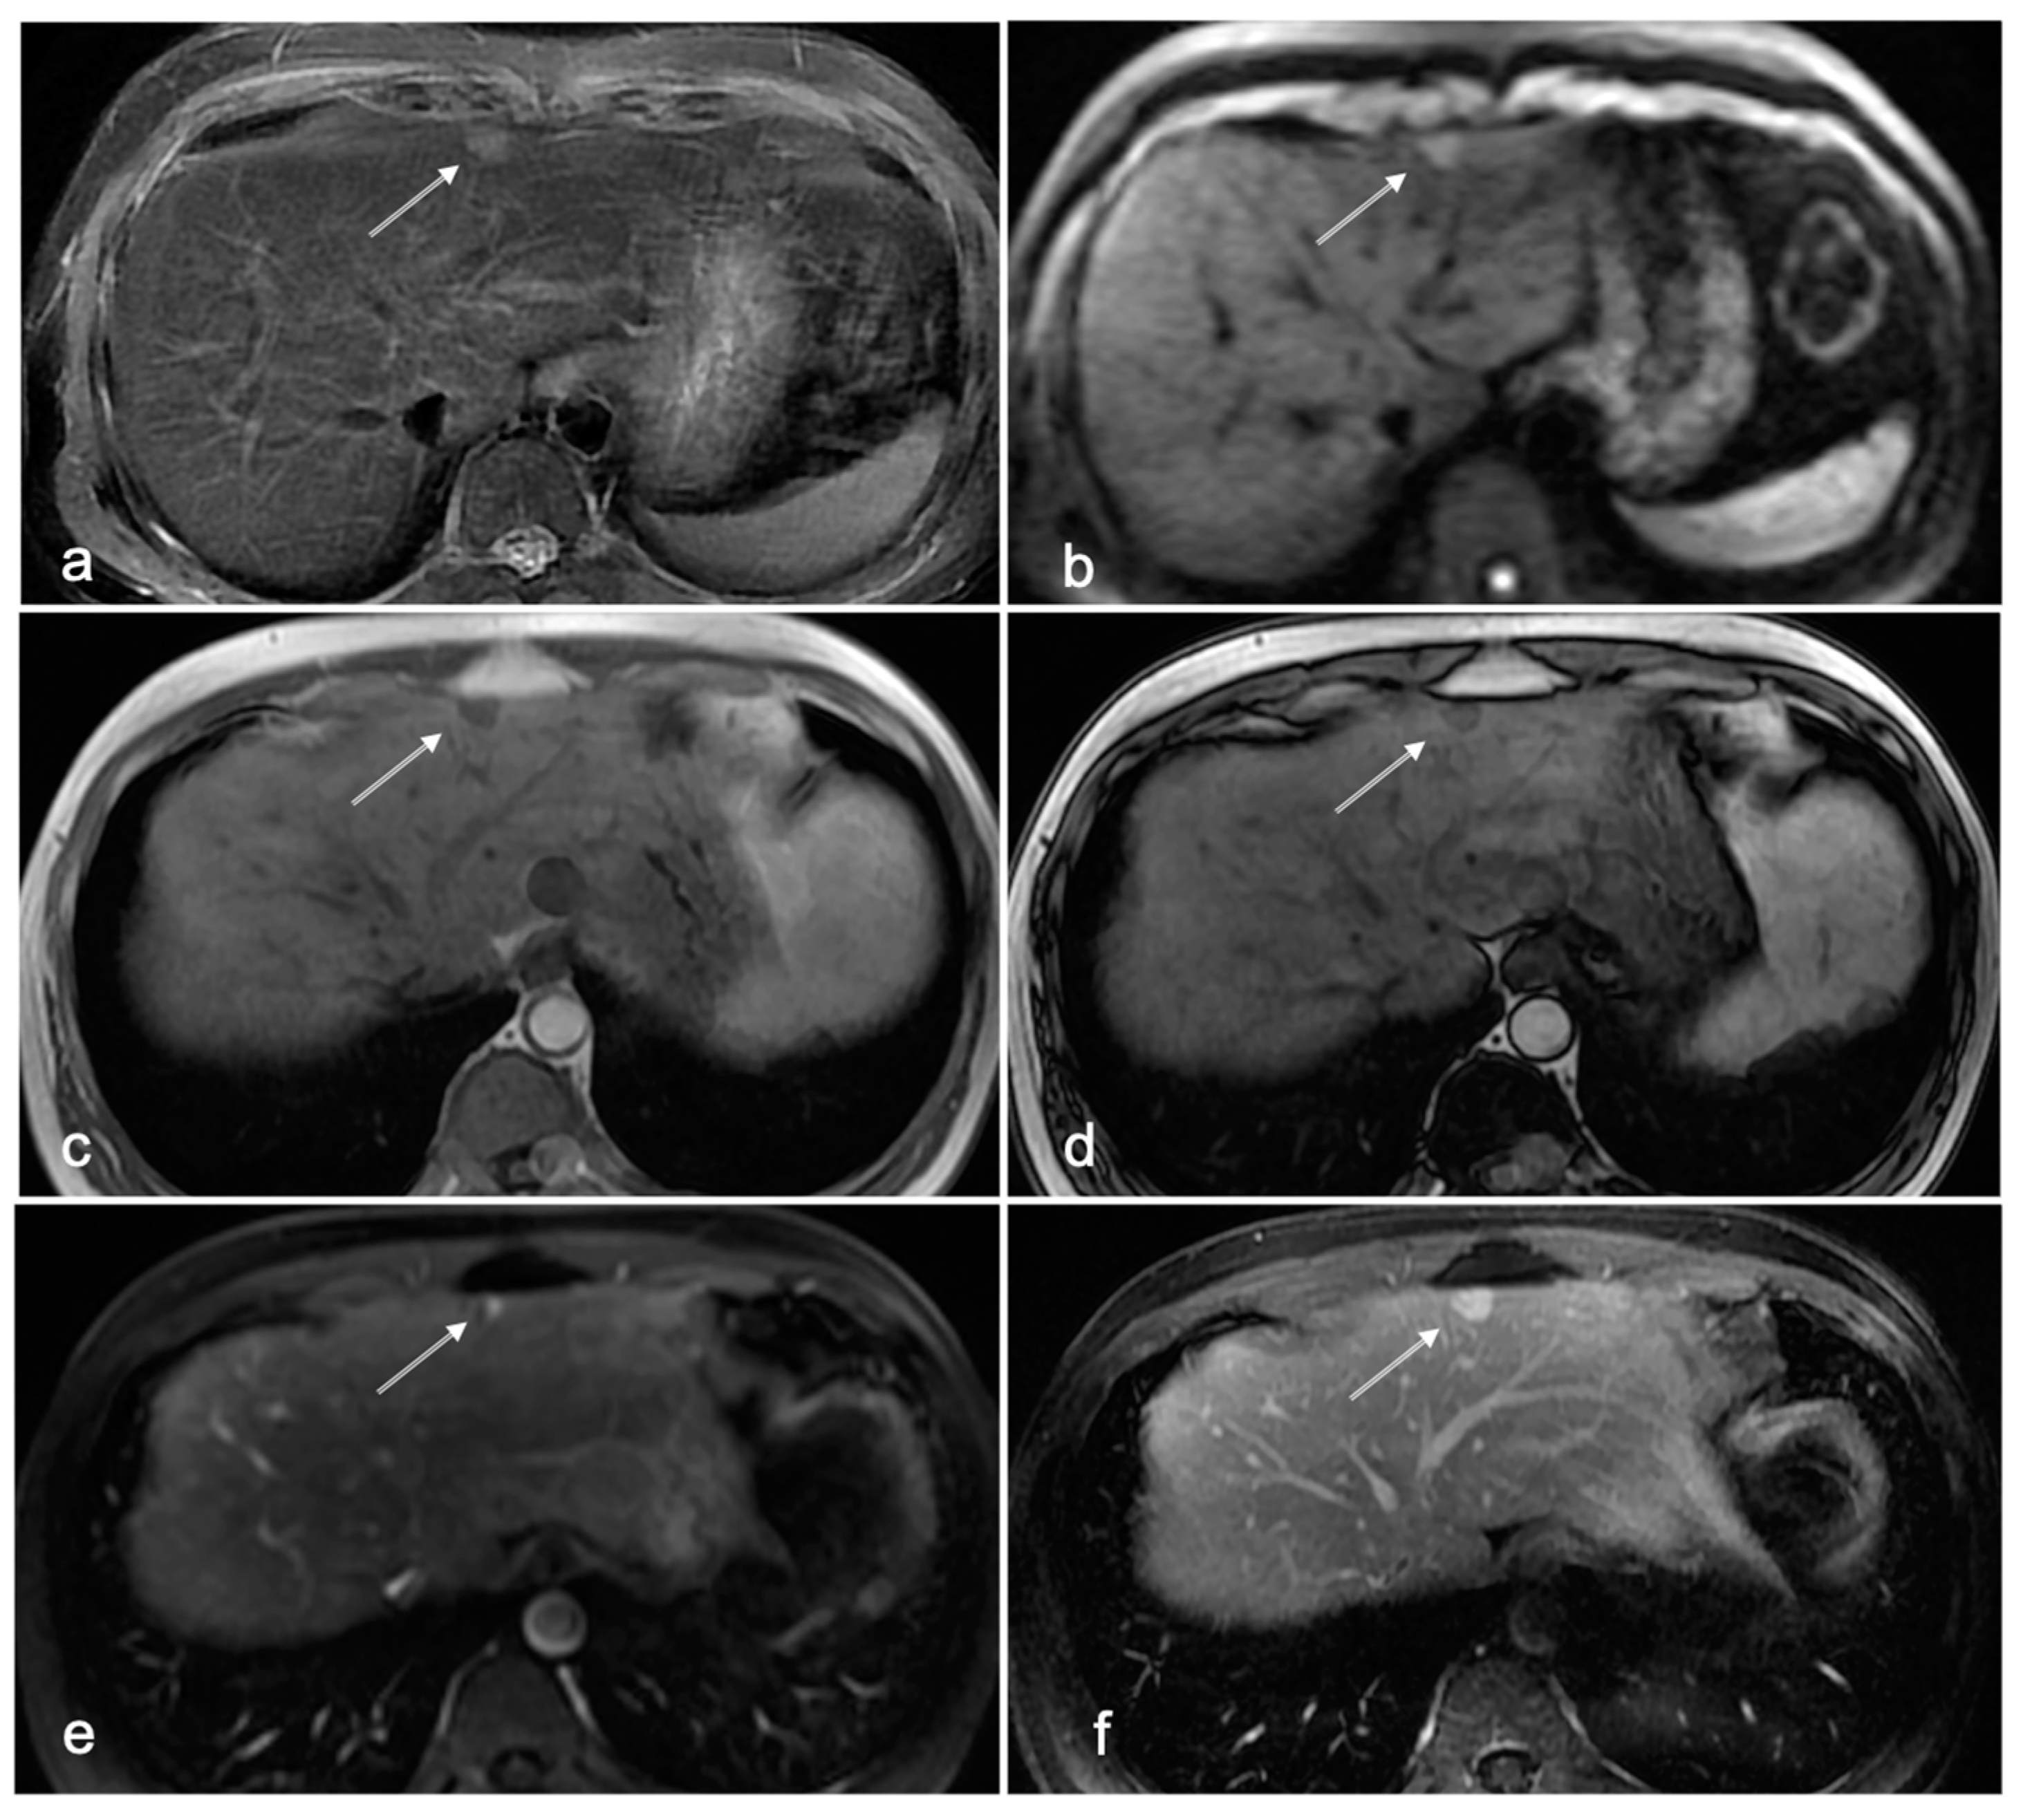

3.1. Cases with HCC